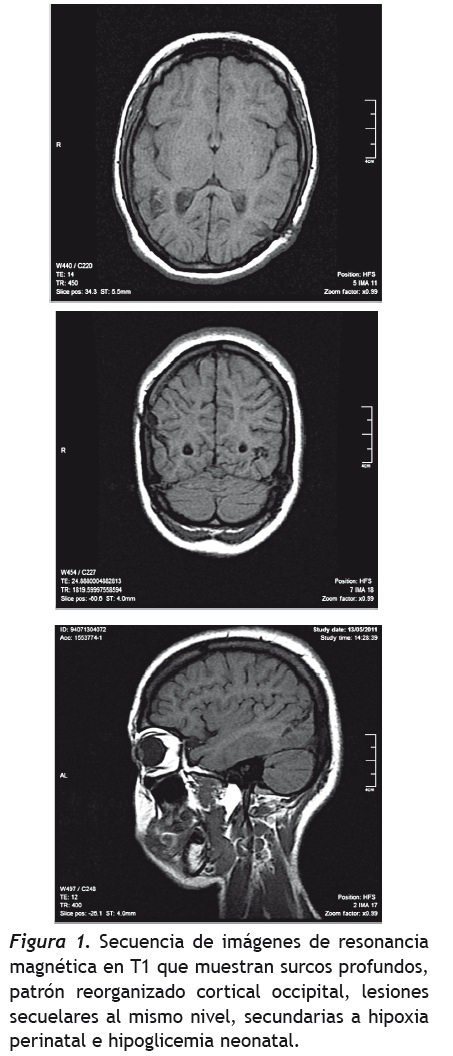

Pero también, cuando las figuras están superpuestas no puede diferenciar una de otra, lo cual corresponde con una alteración en la tercera etapa del modelo cognoscitivo propuesto por Humphreys y Riddoch (1987), la cual implica la integración de la percepción en un conjunto, con la segregación de la figura del fondo y la elaboración de una representación dependiente del punto de vista del sujeto. Riddoch y Humphreys (1987) definen la agnosia integrativa como un trastorno en el que los pacientes con lesiones occipito-temporales bilaterales son incapaces de identificar estímulos en fondos complejos, especialmente cuando se trata de formas superpuestas o entrelazadas. La agnosia integrativa también es asociada con déficits en la codificación del todo a partir de las partes presentes, a pesar de que estos pacientes pueden responder a algunos aspectos indiferenciados de las formas holísticas. Los fallos en el reconocimiento ocurren cuando la descripción holística es insuficiente para la identificación del objeto, siendo el reconocimiento de objetos enteros perturbado por el fracaso en el agrupamiento de las partes (Riddoch & Humphreys, 2003, 2004; Oliveros, 2007). En nuestro caso, en cuanto a las áreas cerebrales afectadas, la paciente presenta un foco epiléptico occipital izquierdo, sin embargo, en las imágenes cerebrales se encuentran alteraciones occipitales bilaterales. Además, se debe tener en cuenta que la paciente presenta una frecuencia elevada de crisis, posiblemente con diferentes vectores de propagación que no solamente deben producir alteraciones ipsilaterales, sino que también deben afectar el hemisferio contralateral, lo cual corresponde a lo planteado por Humphreys & Riddoch respecto a las áreas cerebrales involucradas (1987). Pero por otra parte, en sus desempeños neuropsicológicos, se encuentran estas alteraciones cognitivas que se corroboran con los hallazgos en pruebas como las de figuras superpuestas, ya que no puede integrar la totalidad de los estímulos, por lo que se centra en un detalle específico siendo incapaz de integrarlo con las otras partes que lo conforman y llevándola a generalizaciones erróneas (ej.: al mostrarle una piña se centra únicamente en la parte superior de la misma, asociándola con una palmera, a partir de lo cual empieza a tener intrusiones con elementos del mar, tratando de generalizar su respuesta).